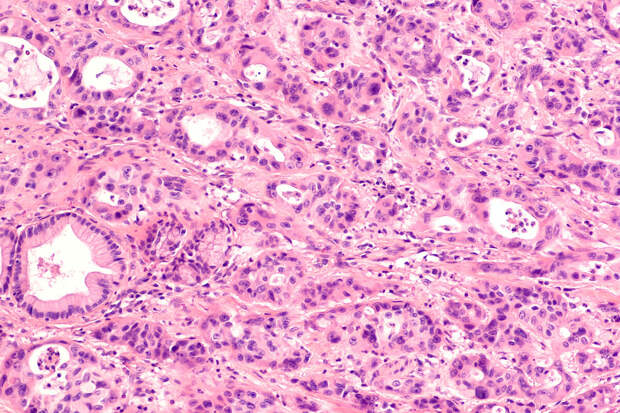

Исследования ученых МИСИС in vitro и in vivo показали отличные результаты – предложенный препарат на основе синтетического пигмента бактериохлорина эффективно подавляет рост опухоли у мышей из экспериментальной группы.

"Исследуемое нами светочувствительное вещество весьма действенно в отношении клеток карциномы легкого Льюиса. Продолжительность жизни мышей увеличилась более чем на 130% по сравнению с контрольной группой, а излечение составило 50%. Фотосенсибилизаторы на основе бактериохлорина обладают высокой фотодинамической эффективностью, вызывают некроз и апоптоз раковых клеток", – пояснил "Газете.

Ru" соавтор исследования, ведущий эксперт НИЦ "Биомедицинской инженерии" Университета МИСИС Саида Каршиева.В дальнейшем ученые планируют продолжить исследования фотосенсибилизатора для ФДТ, но уже для других видов рака, например на данном этапе проходит серия экспериментов in vitro с глиобластомой – злокачественной опухолью, которая наиболее часто образуется в головном мозге.